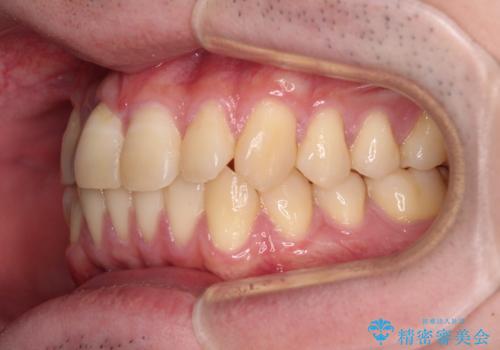

【モニター】前歯のデコボコとクロスバイト ワイヤー矯正で短期間に仕上げる

- 前歯のデコボコとクロスバイトを気にして来院された患者様です。